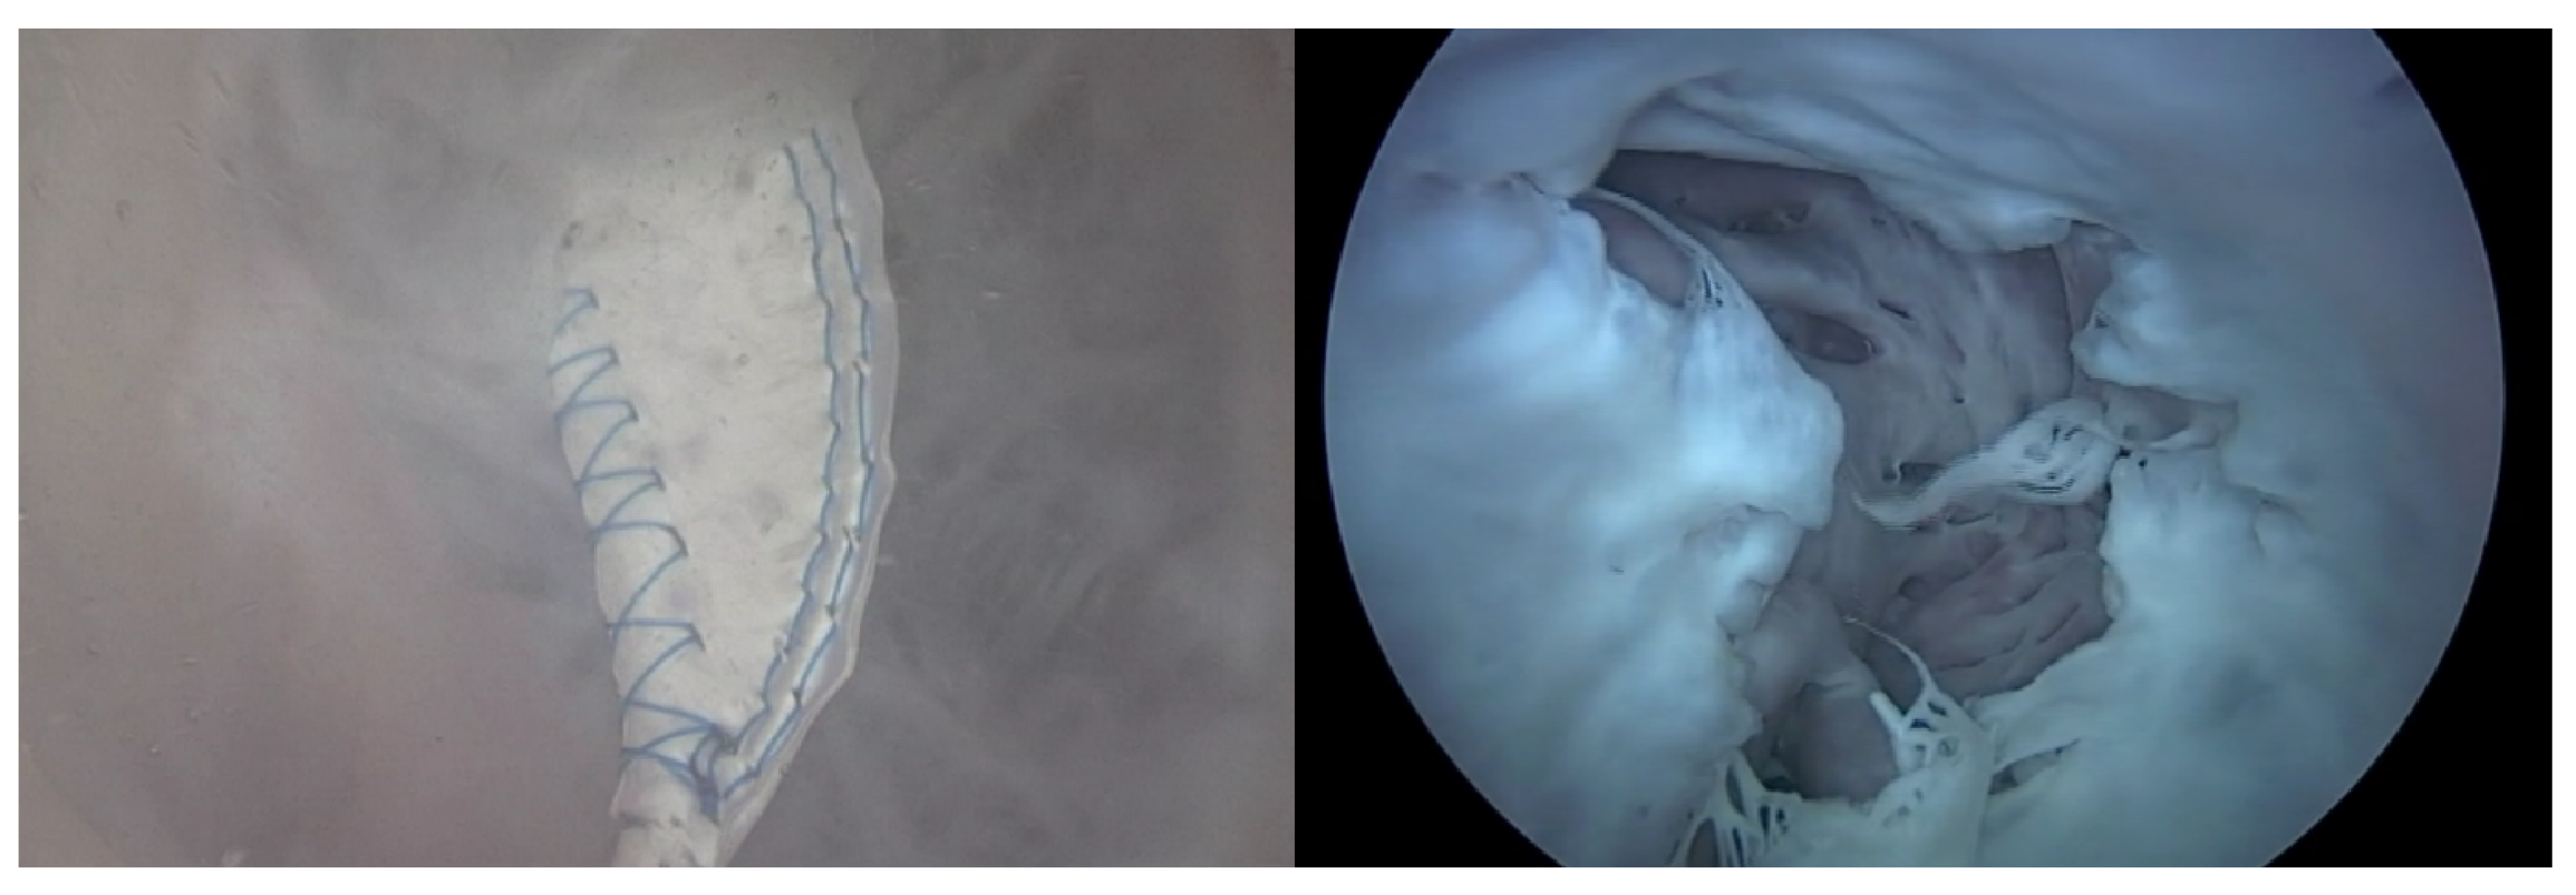

2.1.1. Pivot-TR

The Pivot-TR (Figure 1 and Figure 2), developed by Tau-PNU Medical Co. in Yangsan, Republic of Korea, is an innovative device designed to mitigate TR. It comprises a pivot axis formed from a nitinol wire with components named “the elephant nose” and “the spiral anchor” and a 3D leaflet enveloped in an expanded polytetrafluoroethylene (ePTFE) coating. The spiral anchor is equipped with a hook at the proximal end to allow for the retrieval of the snare at a later time. Positioned at the TV’s intersection point, the device allows for real-time adjustments of its wire tension, enabling clinicians to optimize the angle and position of the pivot axis based on observed blood leakage, thereby reducing TR’s hemodynamic impact [9]. The diameter of the anchor in this study was 35 mm.

Figure 1. Structure (A) and mechanism of Pivot-TR device (B) [9].

Figure 2. The experimental setup and how to use the Pivot-TR device in a heart [9].